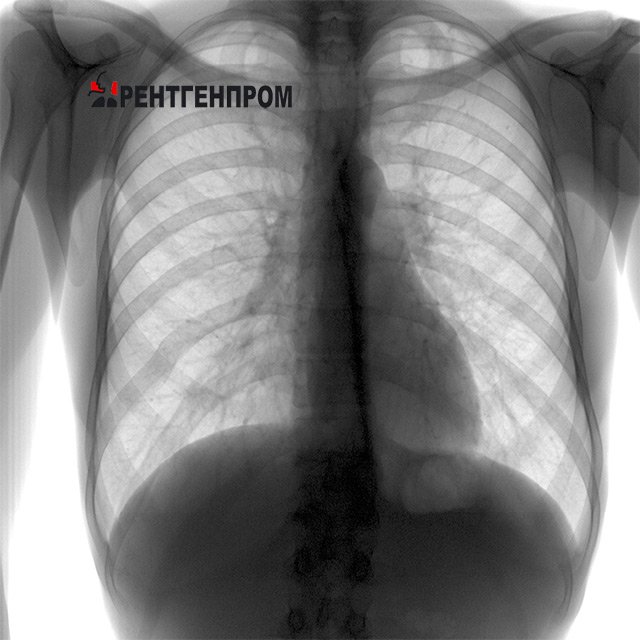

Признаки туберкулёза на снимке

При проведении рентгена лёгких с туберкулёзом на снимке видят признаки развития заболевания различных форм. Например:

• при туберкулёзе лимфатических узлов будет расширен корень лёгких (структуры, входящие в понятие корень), контуры поражённого лёгкого плохо визуализируются, структура органа неоднородная. О наличии или ранее перенесённом туберкулёзе говорят кальцинаты — очаги обызвествления, когда организм самостоятельно борется с возбудителем инфекции;

• при диссеминированном туберкулёзе отмечаются множественные тёмные очаги, они маленькие по размеру и в диаметре не превышают двух миллиметров. Края очагов чёткие, расположены по всему лёгкому, способны к слиянию;

• очаговый туберкулёз характеризуется несколькими участками небольшого размера (до двух сантиметров в диаметре), имеющими округлую или овальную форму. А также склонны к слиянию в крупные образования;

• инфильтративный туберкулёз на снимке лёгких выглядит белыми множественными очагами, имеющими неровные края. Консистенция каждого очага — одинаковая. Располагаются в верхних долях лёгких, образуя дорожку к лёгочному корню;

• казеозная пневмония — одна из тяжёлых форм туберкулёза. Снимок показывает обширные тёмные пятна. На ранней стадии имеют одинаковую гомогенную структуру, а при распаде пятна приобретают собственные более и менее интенсивно окрашенные участки;

• кавернозный туберкулёз — очаговое поражение с распадом из центра повреждённой полости. Отображается очаговым затемнением со светлым центром, имеется дорожка к корню лёгкого;

• диссеминированный плеврит — множественные очаги поражения по всему лёгкому. Имеют чёткие края и не сливаются друг с другом, диаметр около двух-трёх миллиметров, могут обнаруживаться одновременно в нескольких долях лёгкого. image Синдром уплотнения. Очаг низкой и средней плотности. Туберкулез.